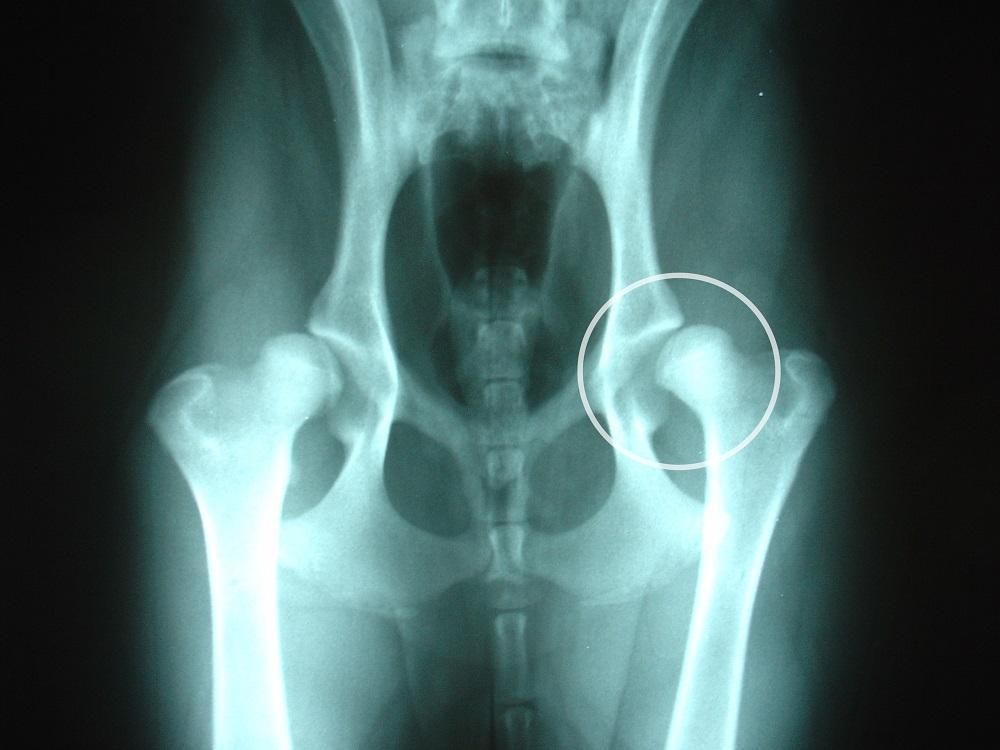

Doenças genéticas do akita - displasia do quadril

A displasia do quadril pode afetar qualquer cachorro, mas é especialmente comum em cachorros de raças grandes. Se trata de uma doença que impede o correto desenvolvimento da articulação durante o crescimento, fazendo com que se desloque lateralmente e com o tempo começa a afetar o movimento normal do cachorro.

Devido a este problema, o cachorro começa tendo muitas dificuldades em realizar as atividades quotidianas dele, sentindo dor e chegando mesmo a mancar. Se trata de uma doença hereditária e como tal, é importante que os criadores que vendem esta raça possam fornecer um certificado que confirme que os progenitores desse filhote não sofrem desta doença.

Para evitar que o akita americano desenvolva displasia do quadril é importante evitar os movimentos bruscos até que o cachorro alcance um ano de idade. Porém, uma vez que o cachorro desenvolva esta doença, você deve seguir exercitando ele para evitar a atrofia muscular. Leia o nosso artigo sobre os exercícios para cachorro com displasia de quadril e não hesite em consultar o seu médico veterinário de confiança para fazer o despiste desta doença.